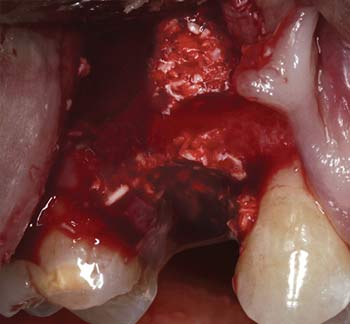

MinerOss Blend cases

grafting for implant placement

MinerOss Blend case 1

MinerOss Blend case provided by Dr. Bach Le